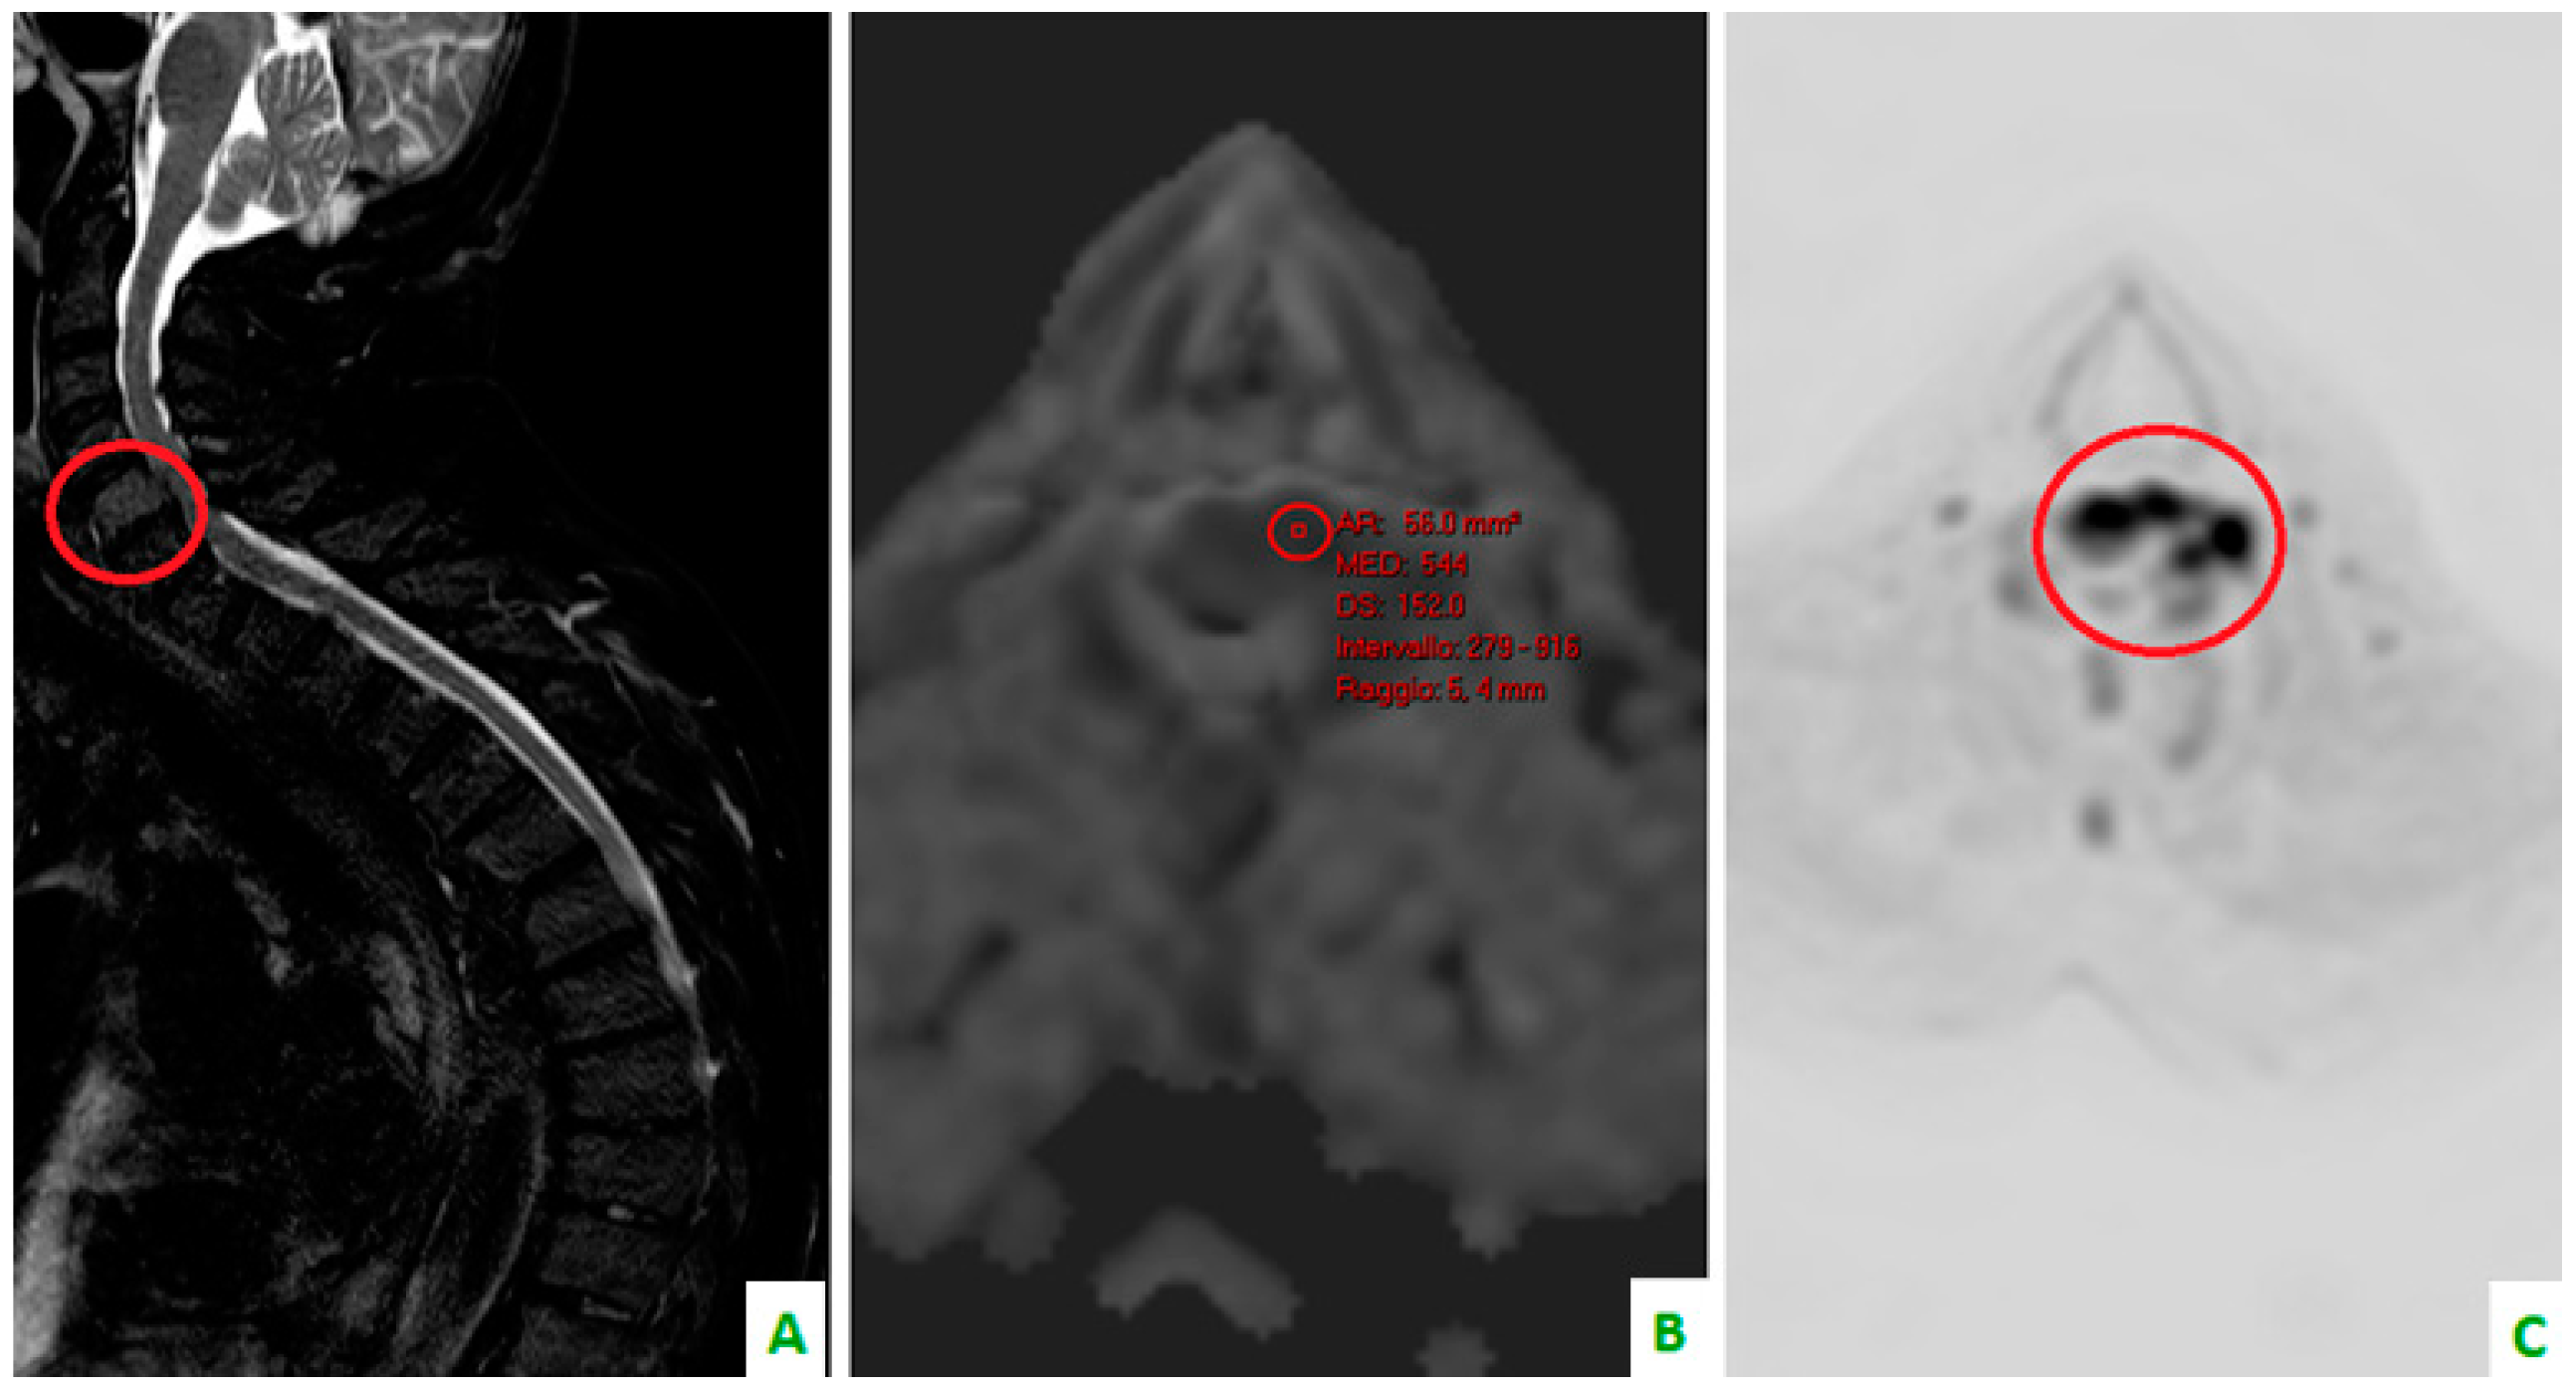

Figure 4. Focus on the red circles: (A) DIXON T2 weighted in the sagittal plane showing bone cervical metastasis (C5) (B) a low apparent diffusion coefficient (ADC) value in the same level, and (C) a restriction of diffusivity.